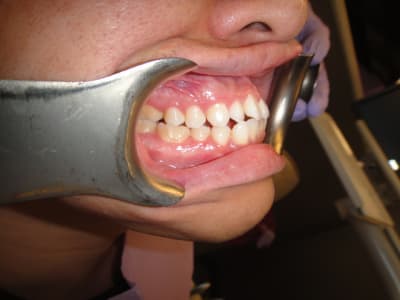

Patient asiatique, 25 ans, consulte car il veut corriger son crossbite bite antérieur localisé aux latérales et son crossbite secteur 2/3. Il aimerait également corriger son apparence générale, son profil notamment.

Classe III squelettique et dentaire.

Pas de shift à la fermeture.

Ci joints photos, ceph, modeles.